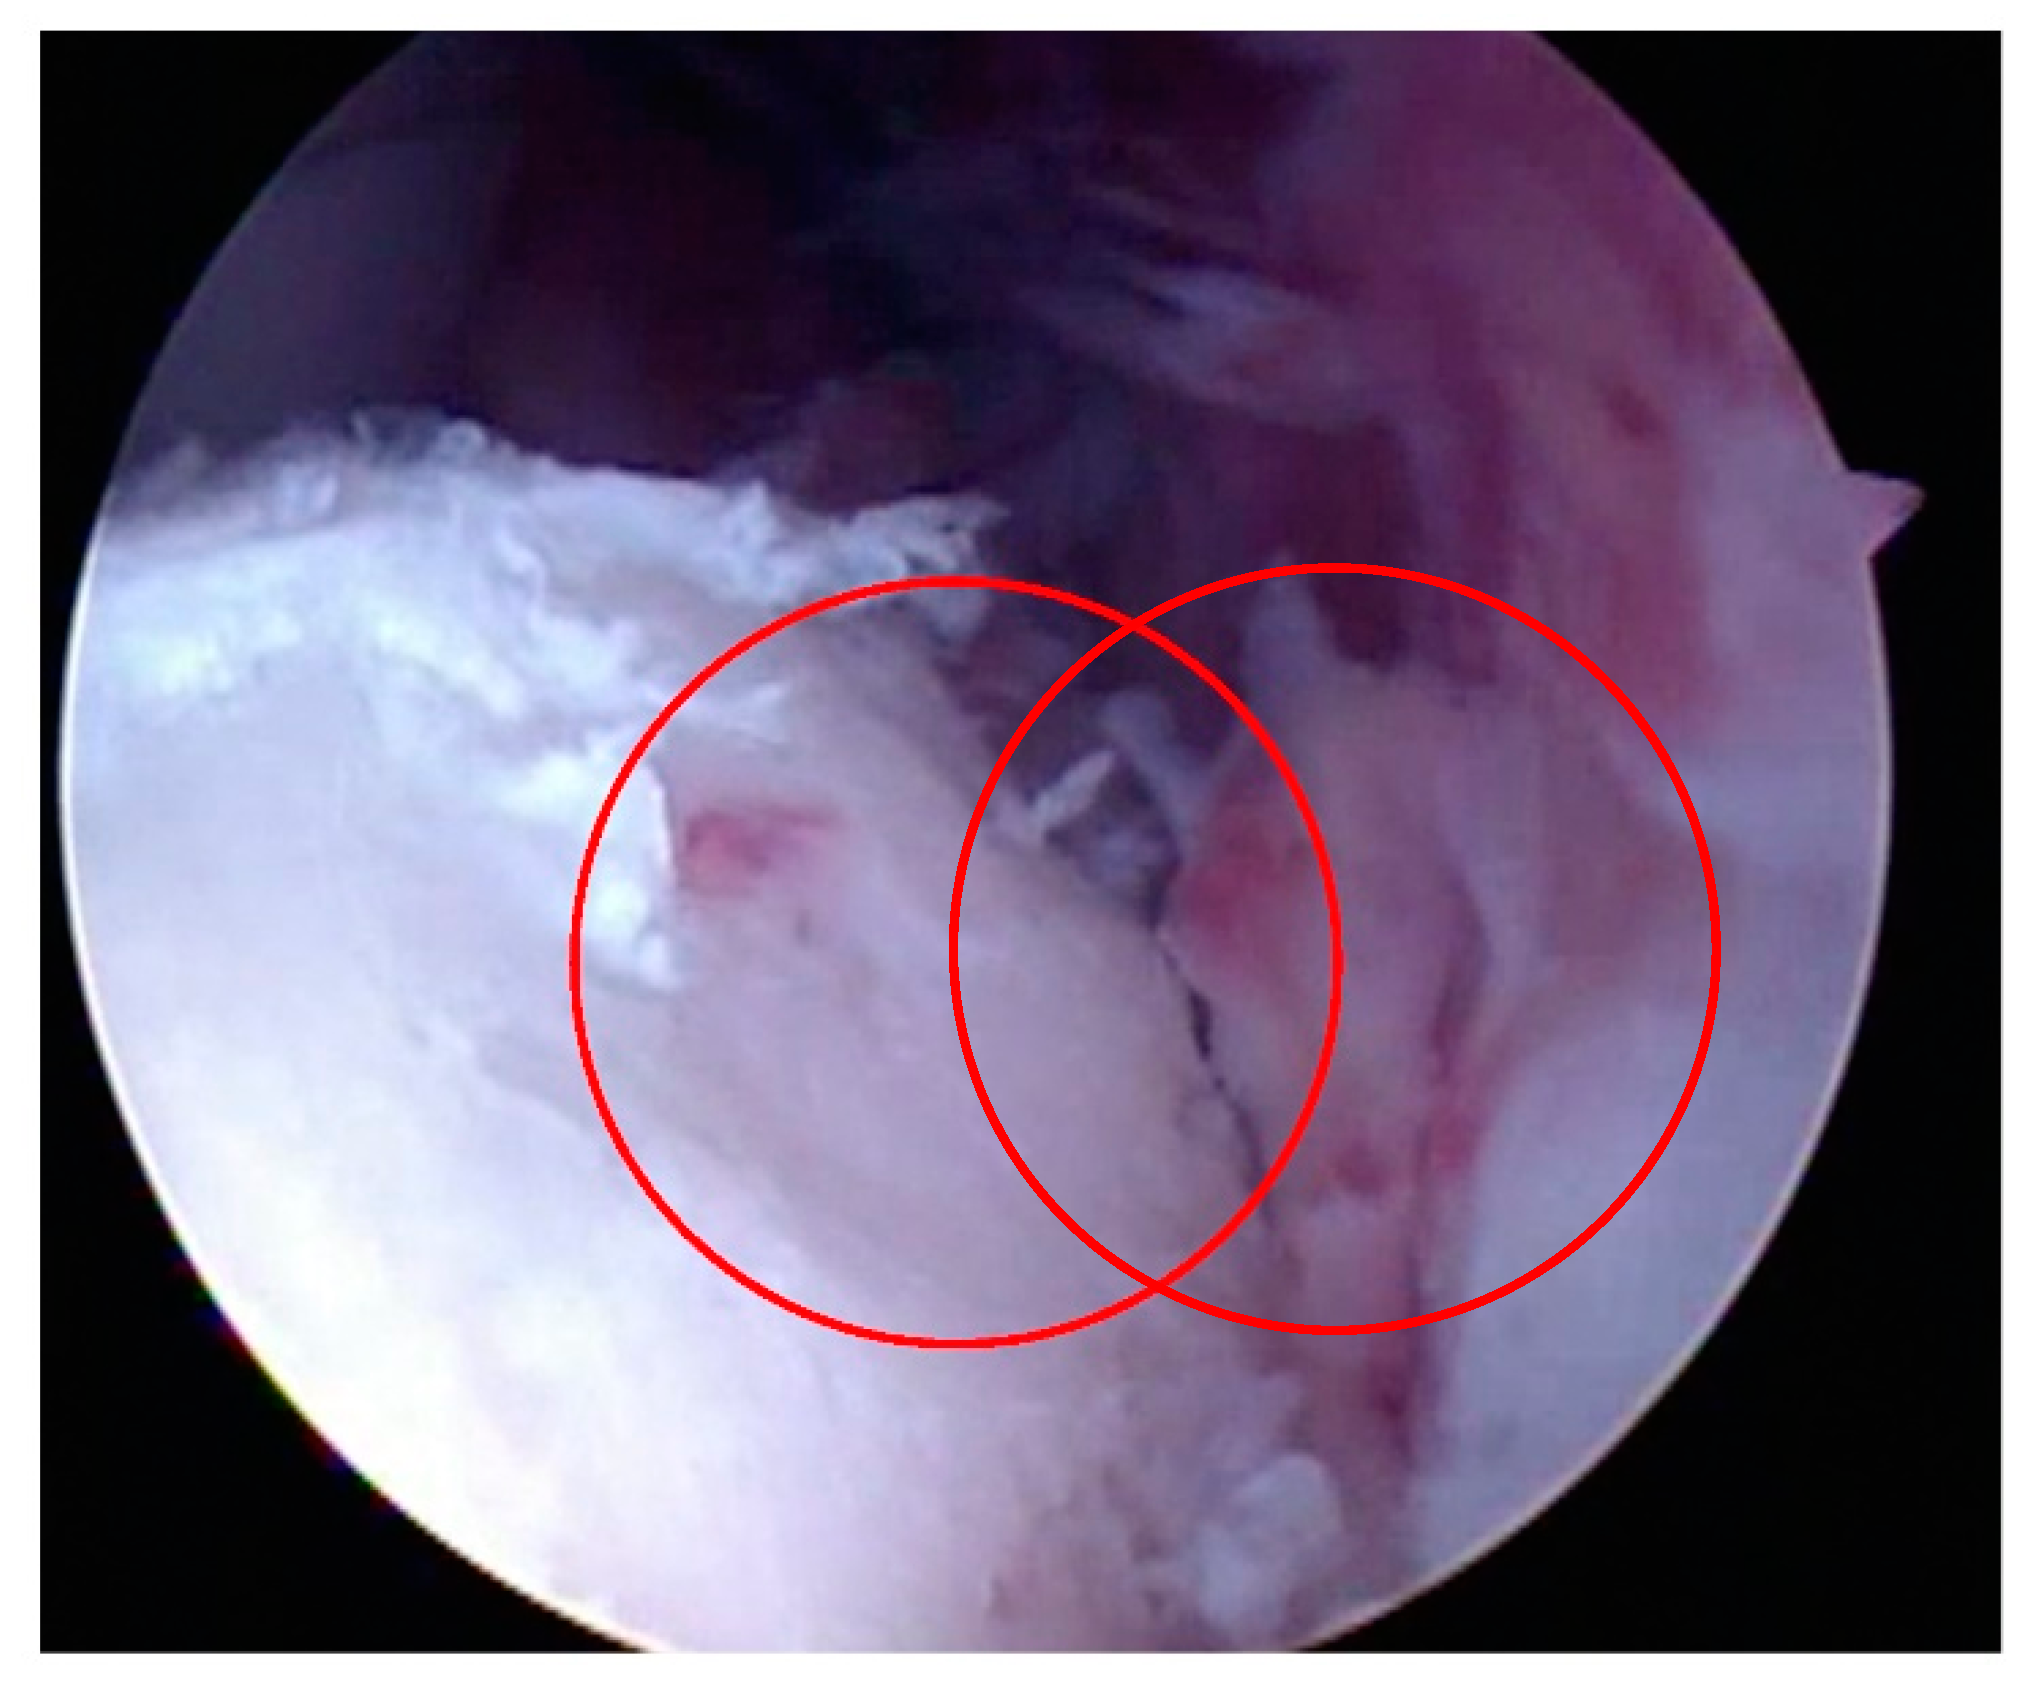

- Articular surface fibrillation (Figure 4)

- Chondral fissures of the articular surface

- Partial erosion of the articular surface (Figure 5)

3.1.6. Large OCD lesions – reattachment of chondral flaps